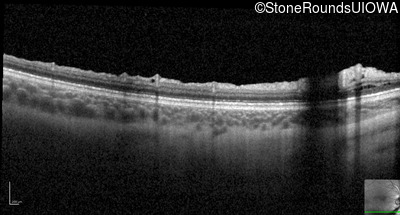

Optical Coherence Tomography - Right - 20/40 -2

Exemplar / OCT Stack